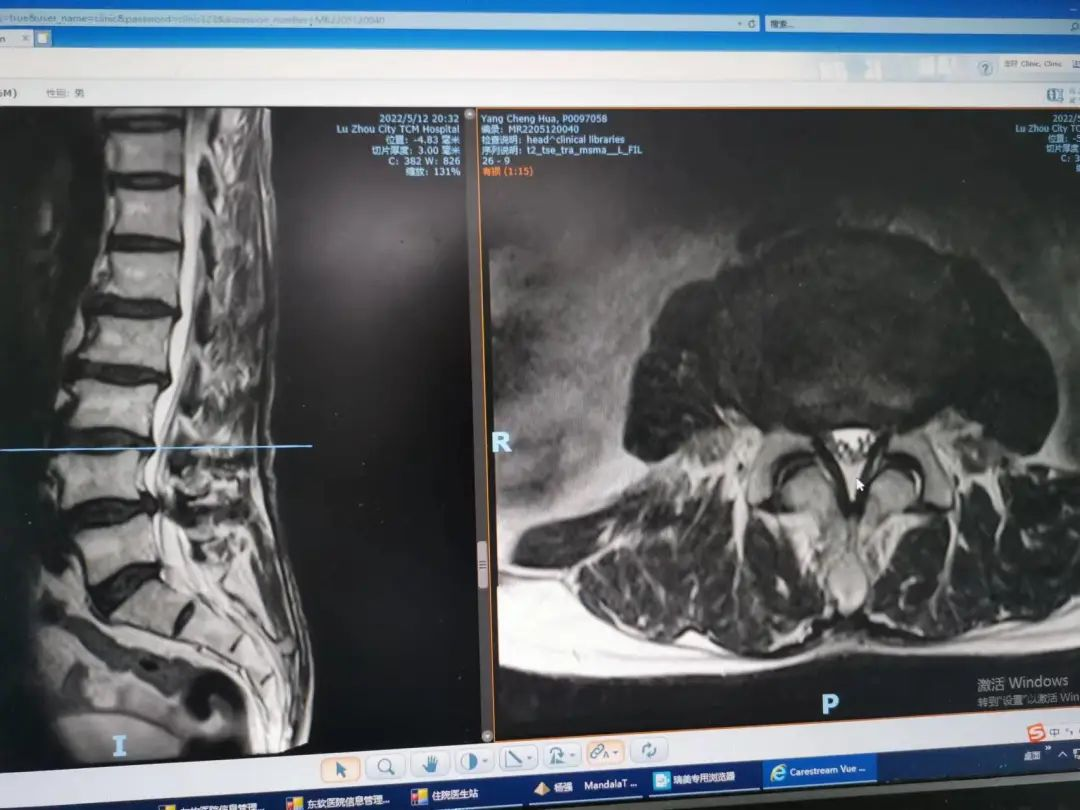

楊先生術(shù)后拍片

由于楊先生是高齡老人,很多脊柱外科醫(yī)生都不敢“觸碰”,對上頸椎手術(shù)更是“望而生畏”,但患者的病情刻不容緩,在科主任楊陳一與主治醫(yī)生楊強的嚴謹細致地配合下,成功為楊先生做了手術(shù)。經(jīng)過數(shù)日的康復治療,楊先生的病情明顯好轉(zhuǎn),現(xiàn)已出院。